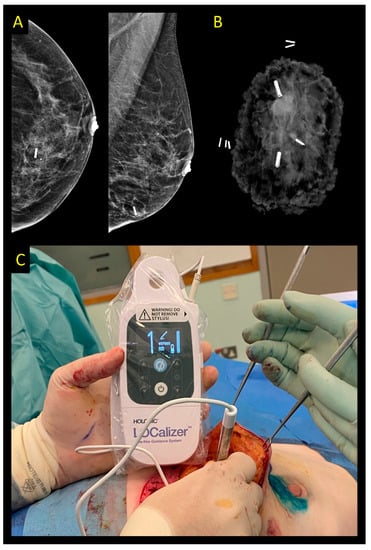

2.5. Radar Reflector Localization

2.6. Radiofrequency Identification Tags